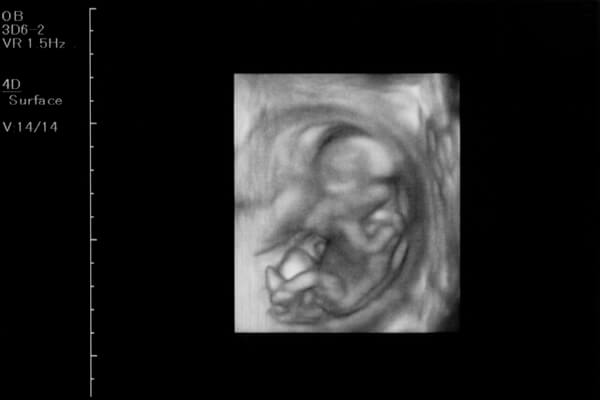

羊水の量が増えて、手足が活発に動かせるようになり、ママのお腹の中でくるくると回転をしています。エコー検査でも良く動く姿が見られるようになりますが、胎動を感じるママはまだ少ないでしょう。

赤ちゃんの外性器はほぼ完成に近づきます。エコー検査で性別を確認できるようになりますが、赤ちゃんの姿勢や角度によっては正確に確認できないこともあります。